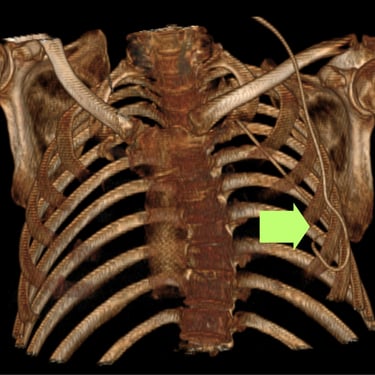

Hidrocefalia y Disfunción de Derivación: Colocación de Derivación Ventrículo-Pleural

La hidrocefalia puede complicarse cuando la derivación ventrículo-peritoneal deja de funcionar correctamente, produciendo aumento de la presión intracraneal y síntomas como cefalea, vómitos, somnolencia o deterioro neurológico. Cuando el peritoneo deja de ser una opción viable debido a infecciones, cirugías previas o mala absorción, se considera la derivación ventrículo-pleural como alternativa efectiva. Este procedimiento permite redirigir el líquido cefalorraquídeo hacia la cavidad pleural, donde puede ser absorbido adecuadamente. La intervención oportuna restablece el drenaje del LCR, reduce la presión intracraneal y mejora el pronóstico del paciente, siendo una solución segura en casos de disfunción peritoneal.